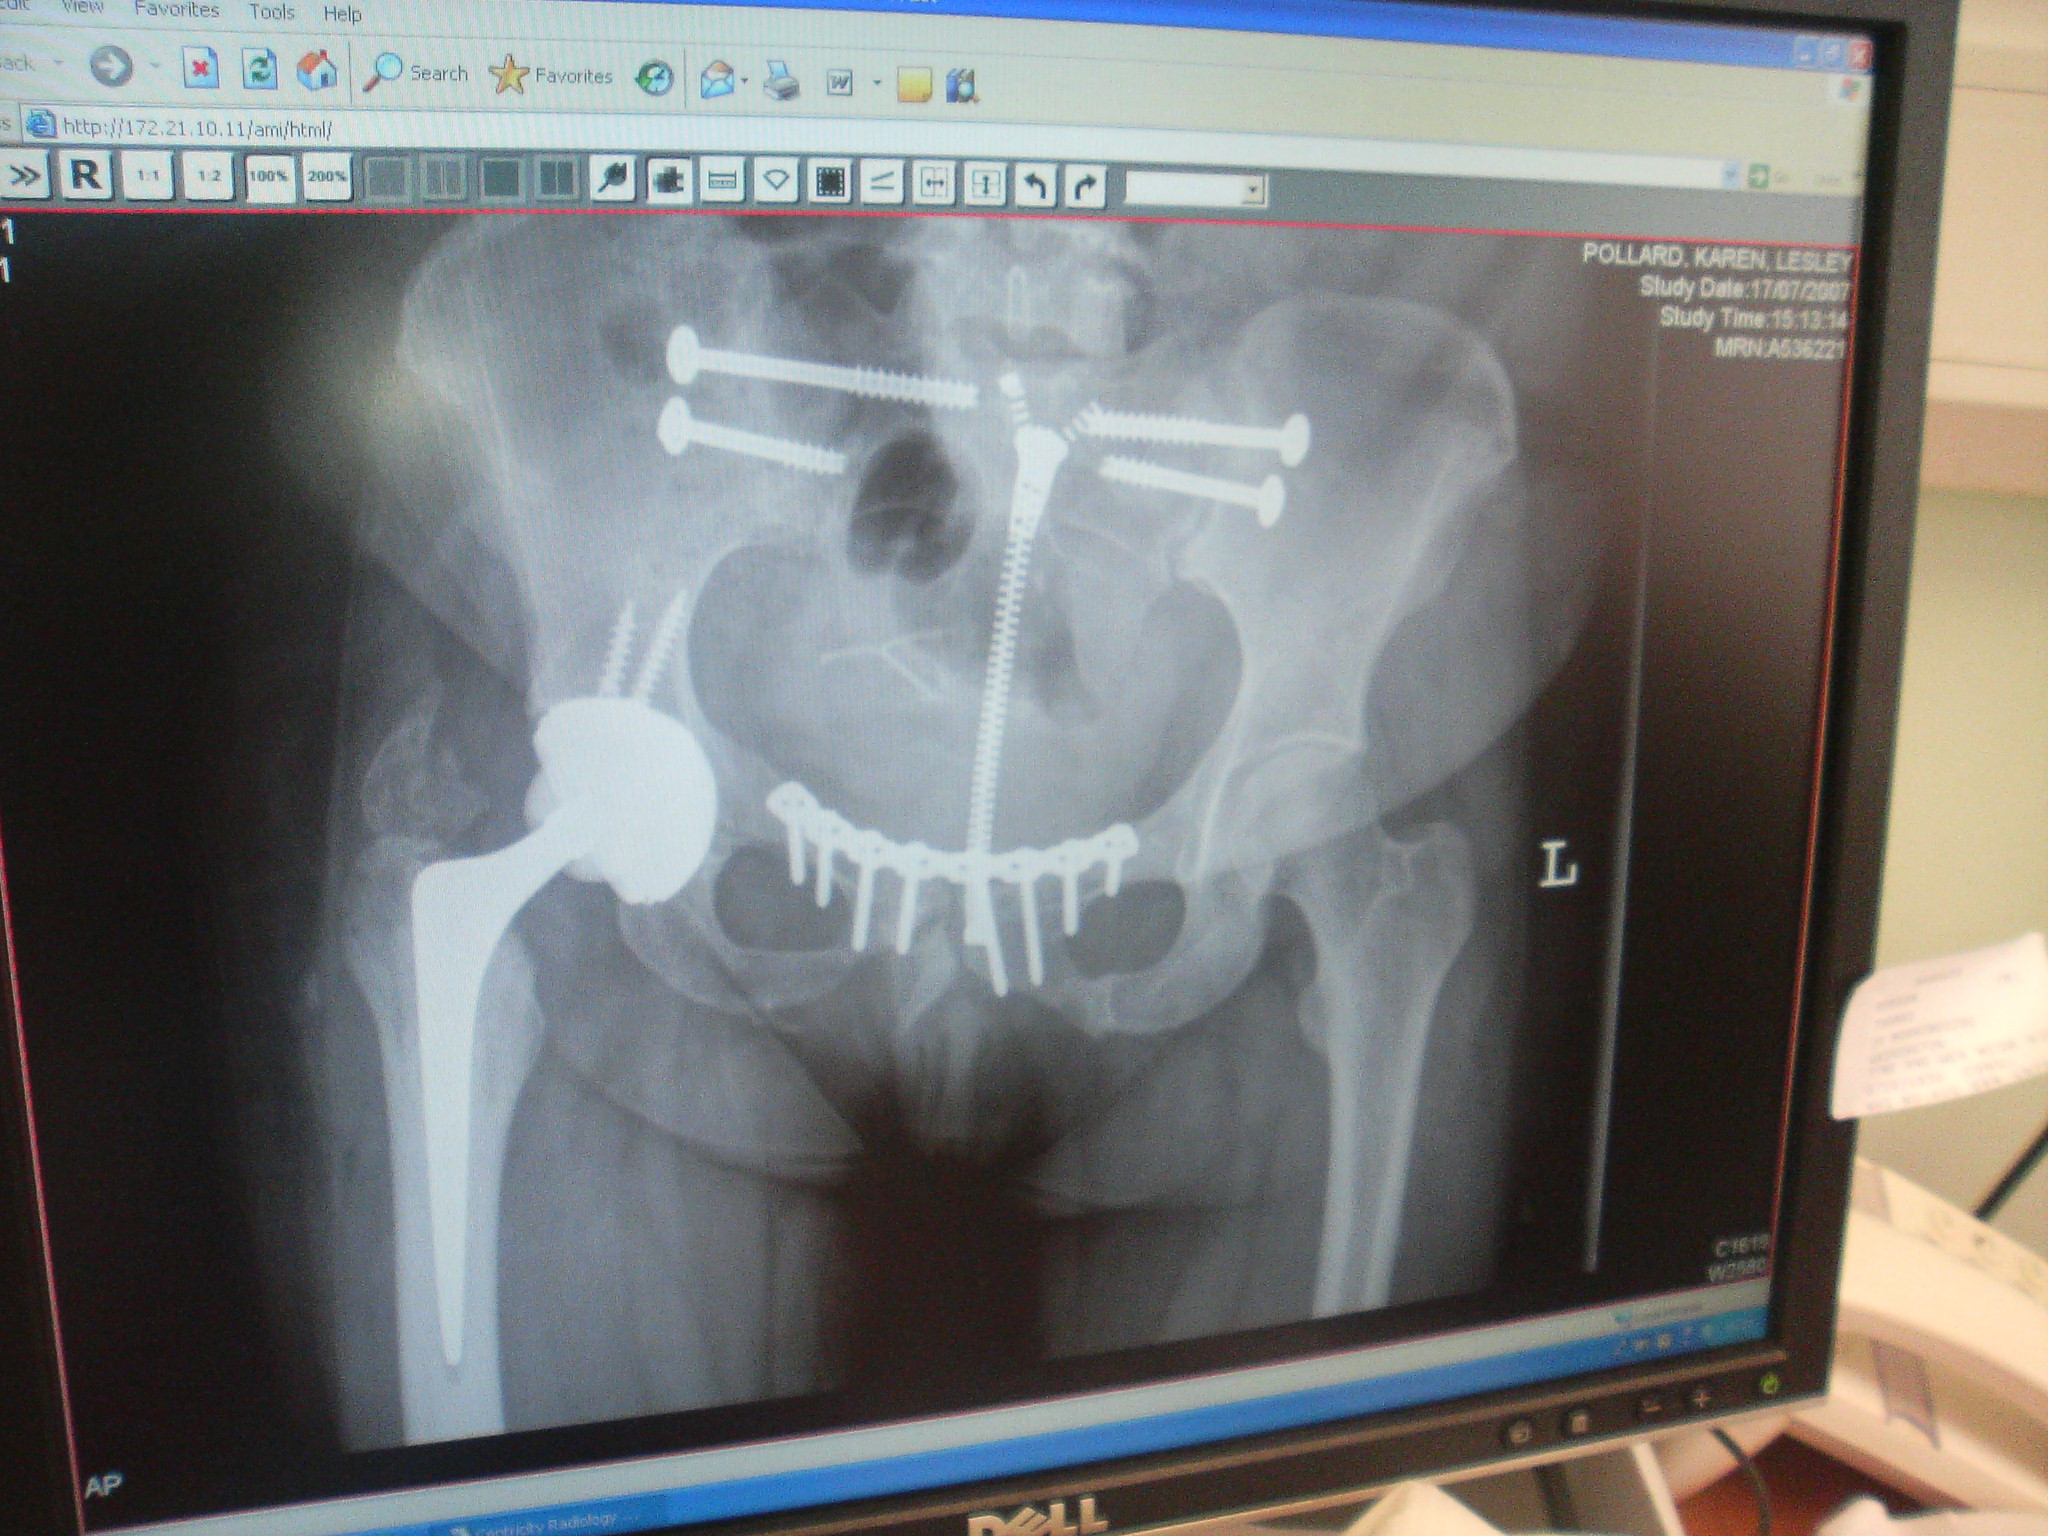

Monday saw kp visit the ortho physio. Went well, and she got discharged from ortho -physio. I met her at the hospital to attend with the orthopedic consultant (who did the Hip op) for a reassessment. She had an X-ray and then we went for a chat with him. He said everything was “as expected” and he was pleased with the x-ray.

Here it is………….

Image136.jpg

Click on the picture to enlarge

Notice the zip they left in her stomach for easy access for any pelvic/hip changes they want to make ;-)

She has to come back in a year.